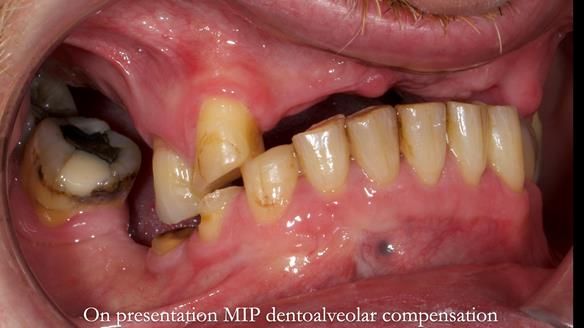

Keith’s combat denture case study

Keith’s case was one of the most challenging and rewarding cases I’ve treated this year. This 64 year old man presented with ill-fitting acrylic partial dentures that lacked stability, retention, and aesthetics. They constantly broke. He had lost the upper front teeth in a road traffic accident in his early 20s. The unopposed teeth had erupted, taking up space. After careful planning, we made a durable, metal-based upper partial denture/splint to address his dental concerns. He loved the outcome.